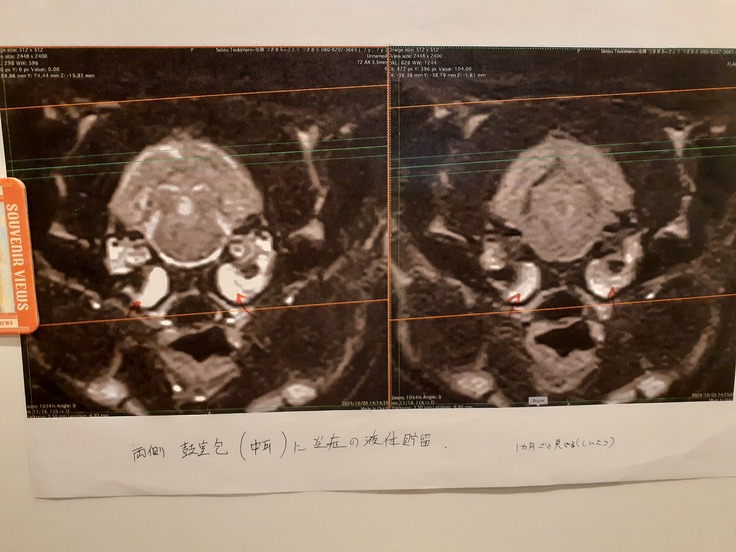

結果としては大脳低形成という脳の発育不良が分かり、MRI検査をしたことで運良く中耳炎が見つかりました。

現在は抗生剤を3か月継続、1月18日にCTをして結果次第では投薬終了、または管を通した排膿をする予定になっています。